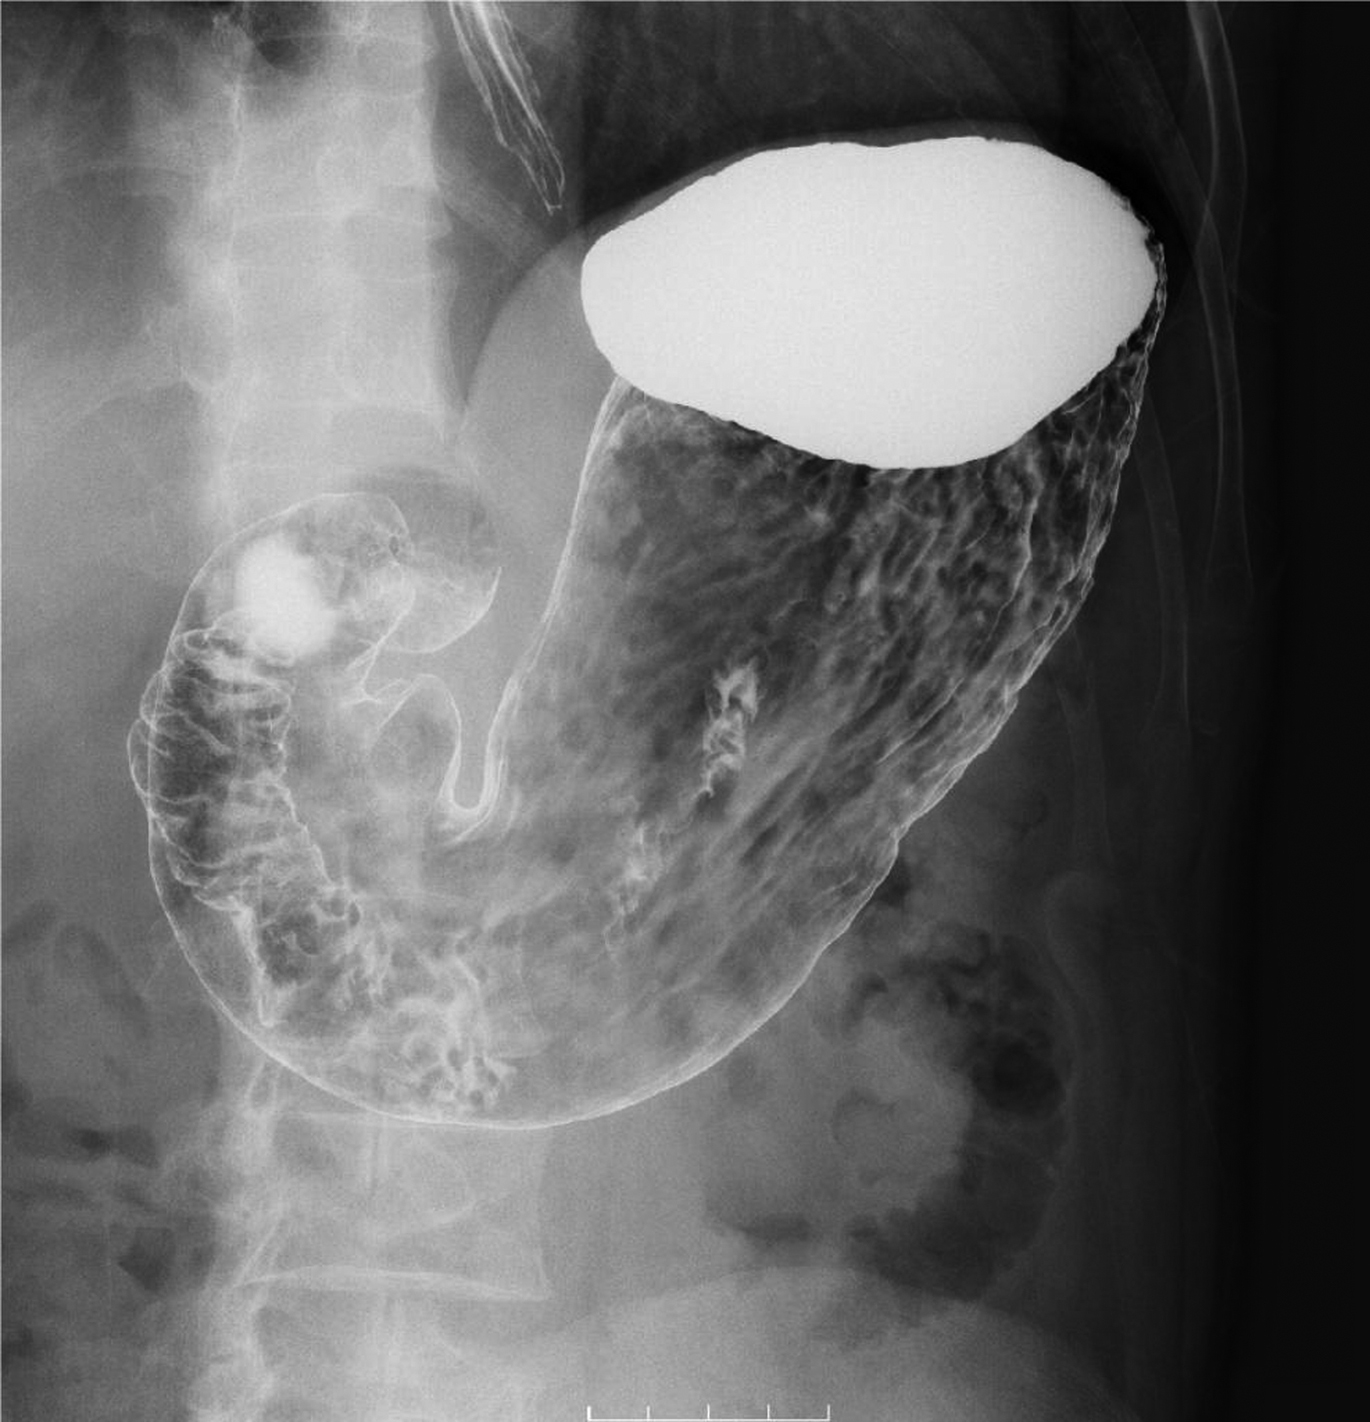

- 消化管造影検査(食道・胃・小腸・大腸検査) 造影剤(バリウム)を使って消化管を観察する検査です。

Q2) どうして胃や大腸の検査の時、回転したり体を動かしたりするのですか?

|

![]() |

A2) 胃や腸の壁の内側にバリウムを付着させて観察する検査なのでムラなく壁全体にバリウムを着けるためです。 |